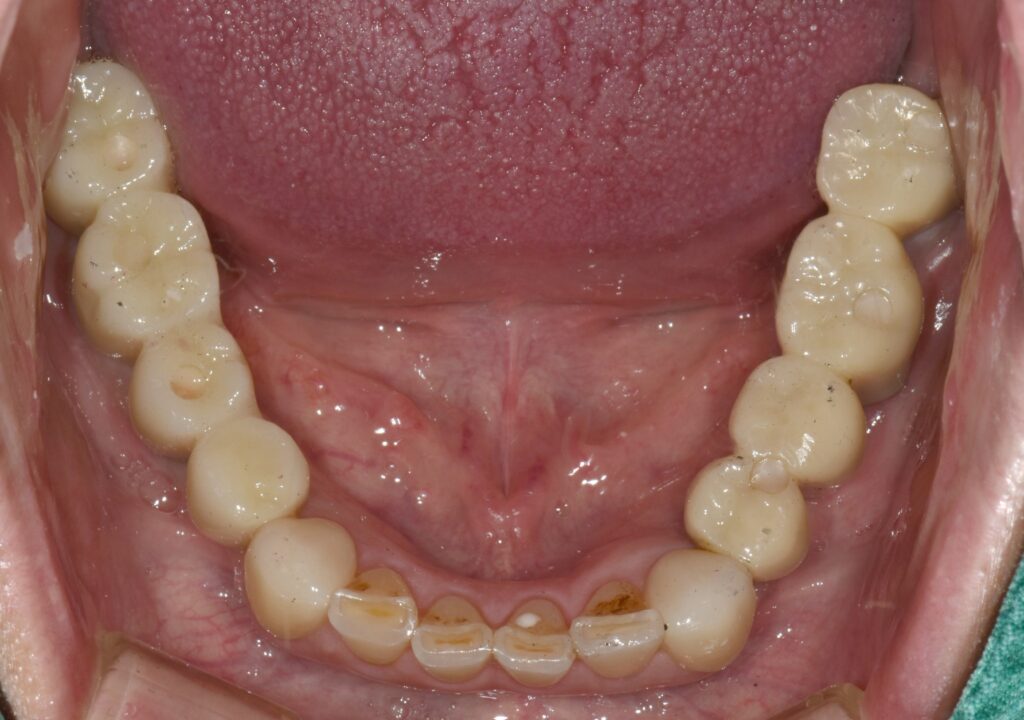

임플란트 식립 후 3개월 뒤에 임플란트와 뼈가 단단하게 붙은 것을 확인한 뒤 본을 떠서 임시치아를 만들었습니다.

1개월 동안 임시치아를 사용하면서 교합(치아가 물리는 관계)을 확인하고 모든 것이 편안해졌을 때 한 번 더 본을 떠서 최종 보철로 이행했습니다.

위와 같이 치료가 완료되었습니다. 상당히 깔끔하게 잘 치료되었네요. 총 치료 기간은 4개월 소요되었습니다.